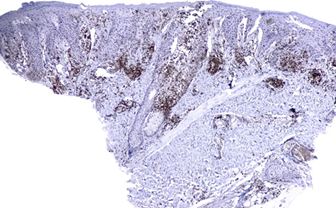

Figure 3. Strong expression CD4+ approximately

90% in a wedge shape, in addition to epidermotropism and folliculotropisms of

cells

Courtesy Dra.

Johanna Brito - LunaPiel